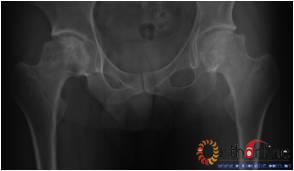

病灶修复情况比较,加用BMP2组病灶修复的完全性及硬化骨数量普遍优于未加BMP2组。(图3)

图3-2 女,30岁,SARS患者骨坏死,(1)术前MRI示双侧骨坏死;右Ⅱc期C3型,左Ⅱb期B型,打压植骨术(加BMP2),(2)5年后CT显示病灶修复好,关节功能优